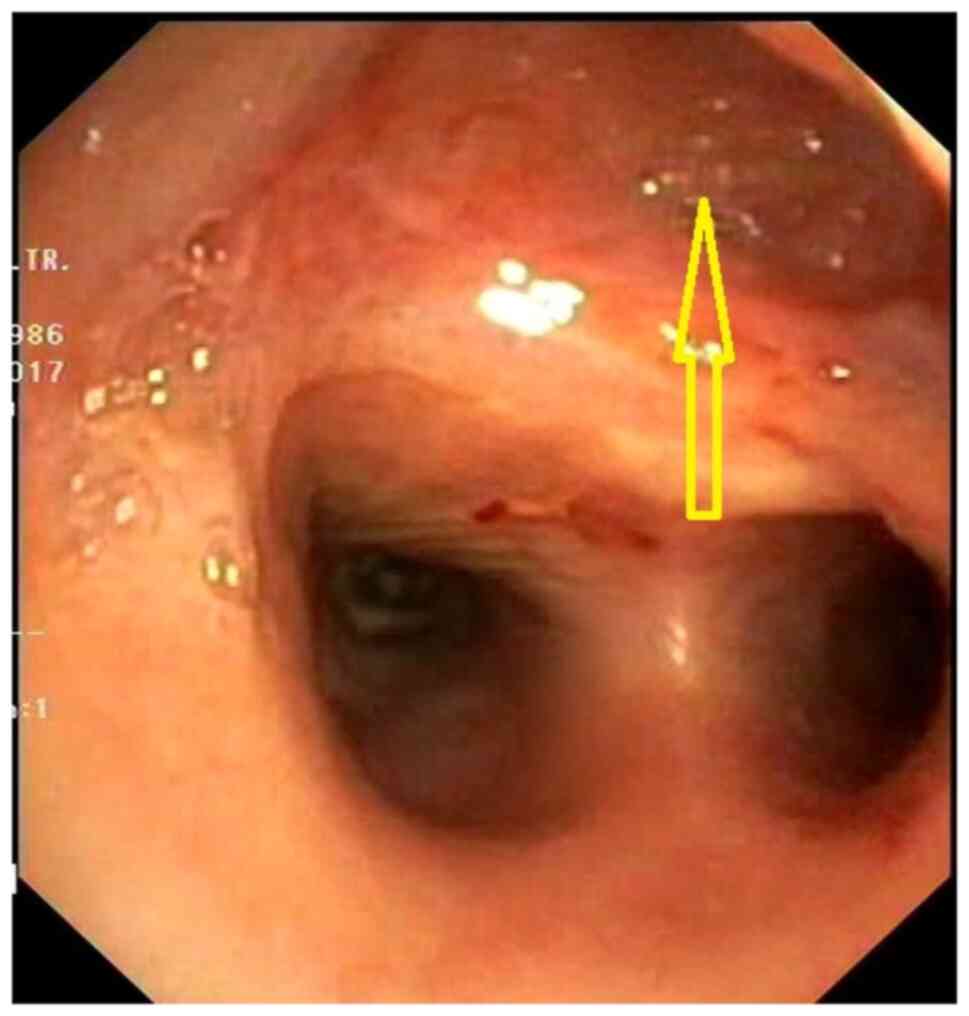

Acquired benign trachea‑oesophageal fistula is a rare benign pathological entity with varying aetiologies that most often occurs post‑intubation. This case report presents the case of a female patient, 31 years old, admitted to the emergency room with sepsis syndrome following bilateral aspiration pneumonia caused by a large trachea‑oesophageal fistula. The fistula was the result of intra‑tracheal migration of an oesophageal stent placed for post lye ingestion stenosis. Esophageal diversion and partial resection with oesophageal patch to repair the tracheal defect, under general anaesthesia with ventilation using rigid bronchoscopy and high frequency jet ventilation (HFJV), followed at a later date by esophageal replacement with colic graft were the procedures performed with a view to curing the patient. In conclusion, complex cases always require a tailored approach. It is important to note that HFJV may be applied for a longer period of time and the oesophagus can be used as patch for the posterior tracheal wall in selected cases. Staged surgery is also an option when the patients' poor health status does not permit major surgery.

Figure 3